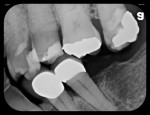

In another case, a 56-year-old man presented with severe bilateral mandibular tori (Figure 9) that made it impossible to take a radiograph using a rigid sensor that captured the entire tooth being evaluated. A flexible phosphor sensor, however, fit the patient’s anatomy with no difficulty or patient discomfort, and a radiograph was easily taken (Figure 10).